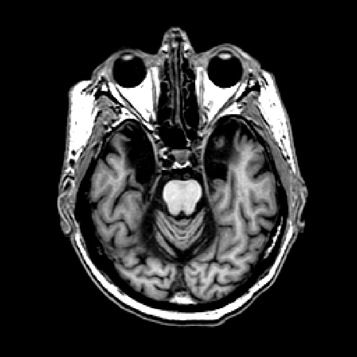

- Bei einer Operation, die HMs Epilepsie lindern sollte, wurde beidseitig fast komplett der Hippocampus entfernt, eine kleine Struktur, die jedoch für das Einspeisen neuer Erinnerungen von zentraler Bedeutung ist.

Der Hippocampus ist der größte Teil des Archicortex und ein Areal im Temporallappen. Er ist zudem ein wichtiger Teil des limbischen Systems. Funktional ist er an Gedächtnisprozessen, aber auch an räumlicher Orientierung beteiligt. Er umfasst das Subiculum, den Gyrus dentatus und das Ammonshorn mit seinen vier Feldern CA1-CA4.

Am 1. September 1953, im Alter von 27 Jahren, wurde Henry Gustav Molaison im Krankenhaus von Hartford in Connecticut betäubt. Dann bohrte der Neurochirurg Wilbur Beecher Scoville zwei Löcher in den Schädel seines Patienten und entfernte auf beiden Seiten des Gehirns ein Stück des Schläfenlappens. Es war eine Operation, die Molaison weltberühmt machen sollte, weil er damit sein Gedächtnis und seine Identität verlor.

Offenbar hatte Karl Lashley bei seinen Studien am falschen Ort gesucht. In seinen Rattenexperimenten hatte er stets Teile der Hirnrinde, also der äußersten Schicht des Gehirns entfernt. Dieses Hirnareal ist in der Entwicklungsgeschichte des Gehirns das jüngste, alle anderen hielt Lashley für zu primitiv. H.M. fehlte es aber nicht an Hirnrinde, Scoville hatte einen Teil des Mandelkerns, der Amygdala, entfernt und fast den gesamten Hippocampus. Diese Region an der Innenseite der Schläfenlappen war offenbar entscheidend für das Formen neuer Erinnerungen.

Eine weitere Merkwürdigkeit im Fall H.M: Ihm fehlte zwar das Langzeitgedächtnis, aber für ein paar Sekunden konnte er sich alles merken. Viele Versuche haben gezeigt, dass sein Kurzzeitgedächtnis in etwa so gut funktionierte wie das eines gesunden Menschen. Telefonnummern oder Wortlisten etwa konnte H.M. sich kurze Zeit merken, wurde er aber nach ein paar Minuten oder Stunden noch einmal gefragt, hatte er sie vergessen. „H.M. war der Paradefall, der gezeigt hat, dass der Hippocampus zentral ist für die Übertragung vom Kurzzeit– ins Langzeitgedächtnis“, sagt Markowitsch. Was auf lange Zeit abrufbar bleiben soll, das muss offenbar durch das Nadelöhr des Hippocampus. So haben Forscher mit bildgebenden Verfahren gezeigt, dass sich Menschen aus einer Liste von Wörtern an die am besten erinnern, bei deren Lernen der Hippocampus am stärksten aktiv war.

Molaison starb am 2. Dezember 2008 in einem Altersheim in Connecticut. Sein Leichnam wurde sofort ins Massachusetts General Hospital in Charlestown gebracht, wo Forscher unter anderem des Brain Observatory in San Diego die Nacht durcharbeiteten, um Gehirnscans anzufertigen und H.M.s Gehirn für die Nachwelt zu erhalten. Henry Molaison selbst konnte keine neuen Erinnerungen mehr formen, aber in der Welt der Wissenschaft hat er bleibende Spuren hinterlassen.